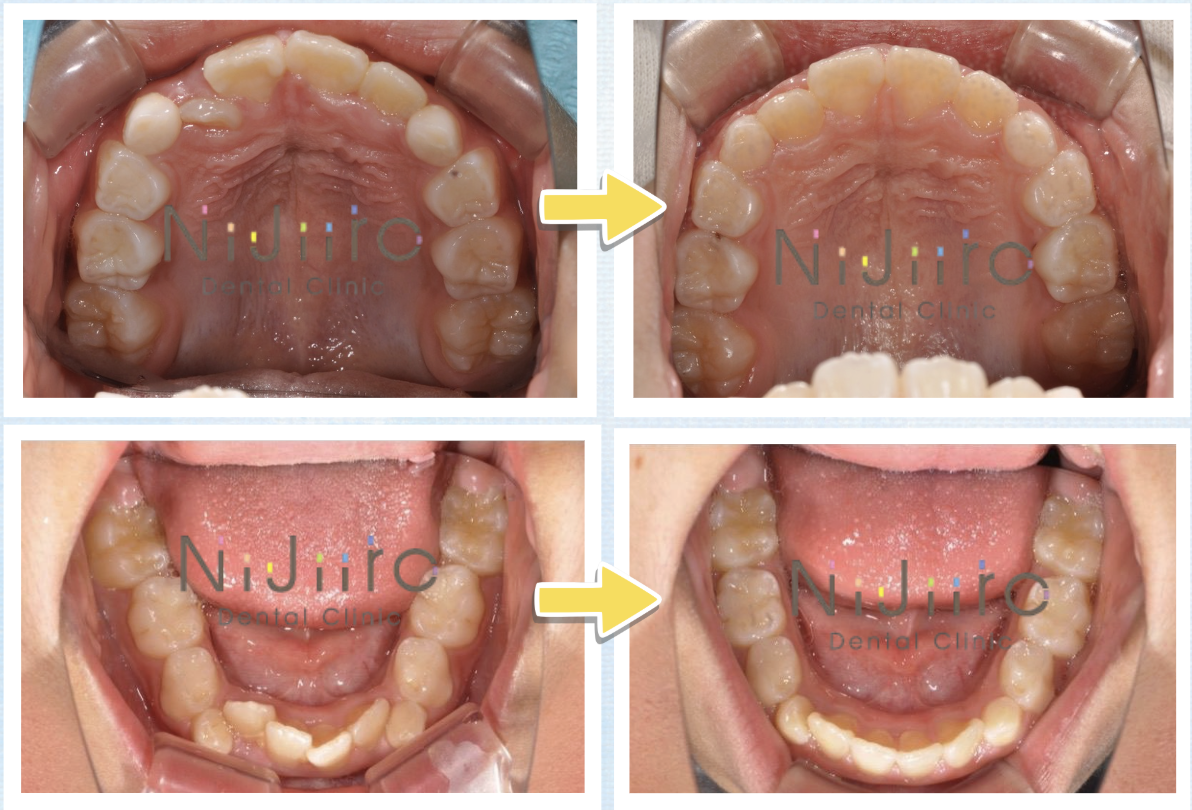

【症例イメージ】顎のスペース不足で「ガタガタ」になってしまったケース

ここで、一期治療によってどのように歯並びの土台が作られるのか、よくある症例のイメージをご紹介します。

■ お悩み: 「前歯が大人の歯に生え変わったが、斜めに生えて重なっている(ガタガタしている)」

■ 原因: 乳歯の段階で歯と歯の間に隙間がなく、顎の幅が全体的に狭かったため、後から生えてきた大きな永久歯が並ぶスペースが不足していました。

■ 結果: 矯正治療で顎の骨が適切に成長し、永久歯がきれいに並ぶための十分なスペース(ベッド)が確保されました。その結果、重なっていた前歯が自然と正しい位置に並びやすくなりました。

このように、「スペースがないなら、顎を育ててスペースを作る」というのが一期治療の基本的なアプローチです。